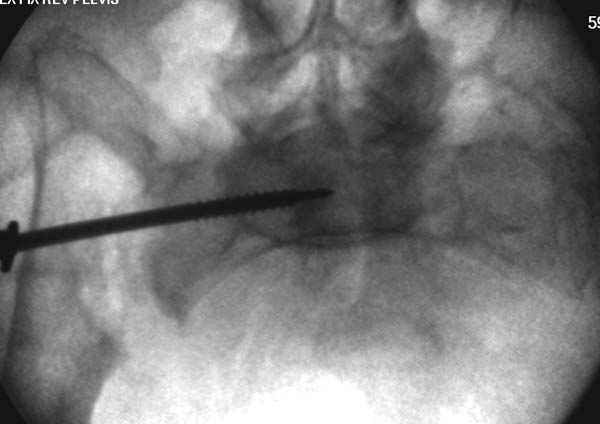

Вход в таз

На картинке, для репозиции свежих разрывов в КПС мы применяем такой способ. За скобу через блок. Груз достаточно большой. Перед этим опускаем головной конец в качестве противотяги, т.к. промежностный упор не используем. Обычно тяги хватает. Попробуйте.

Большое спасибо всем Вам за помощь! Вчера прооперировали пациентку. Выполнили закрытую репозицию левой половины таза на тракционном столе под контролем ЭОП, закрытая фиксация левого КПС двумя каннулированными винтами. Учитывая удовлетворительное стояние отломков лонной и седалищной костей справа, а так же удовлетворительную ширину лона передние отделы стабилизировали системой ЦИТО

Винты введены в S1